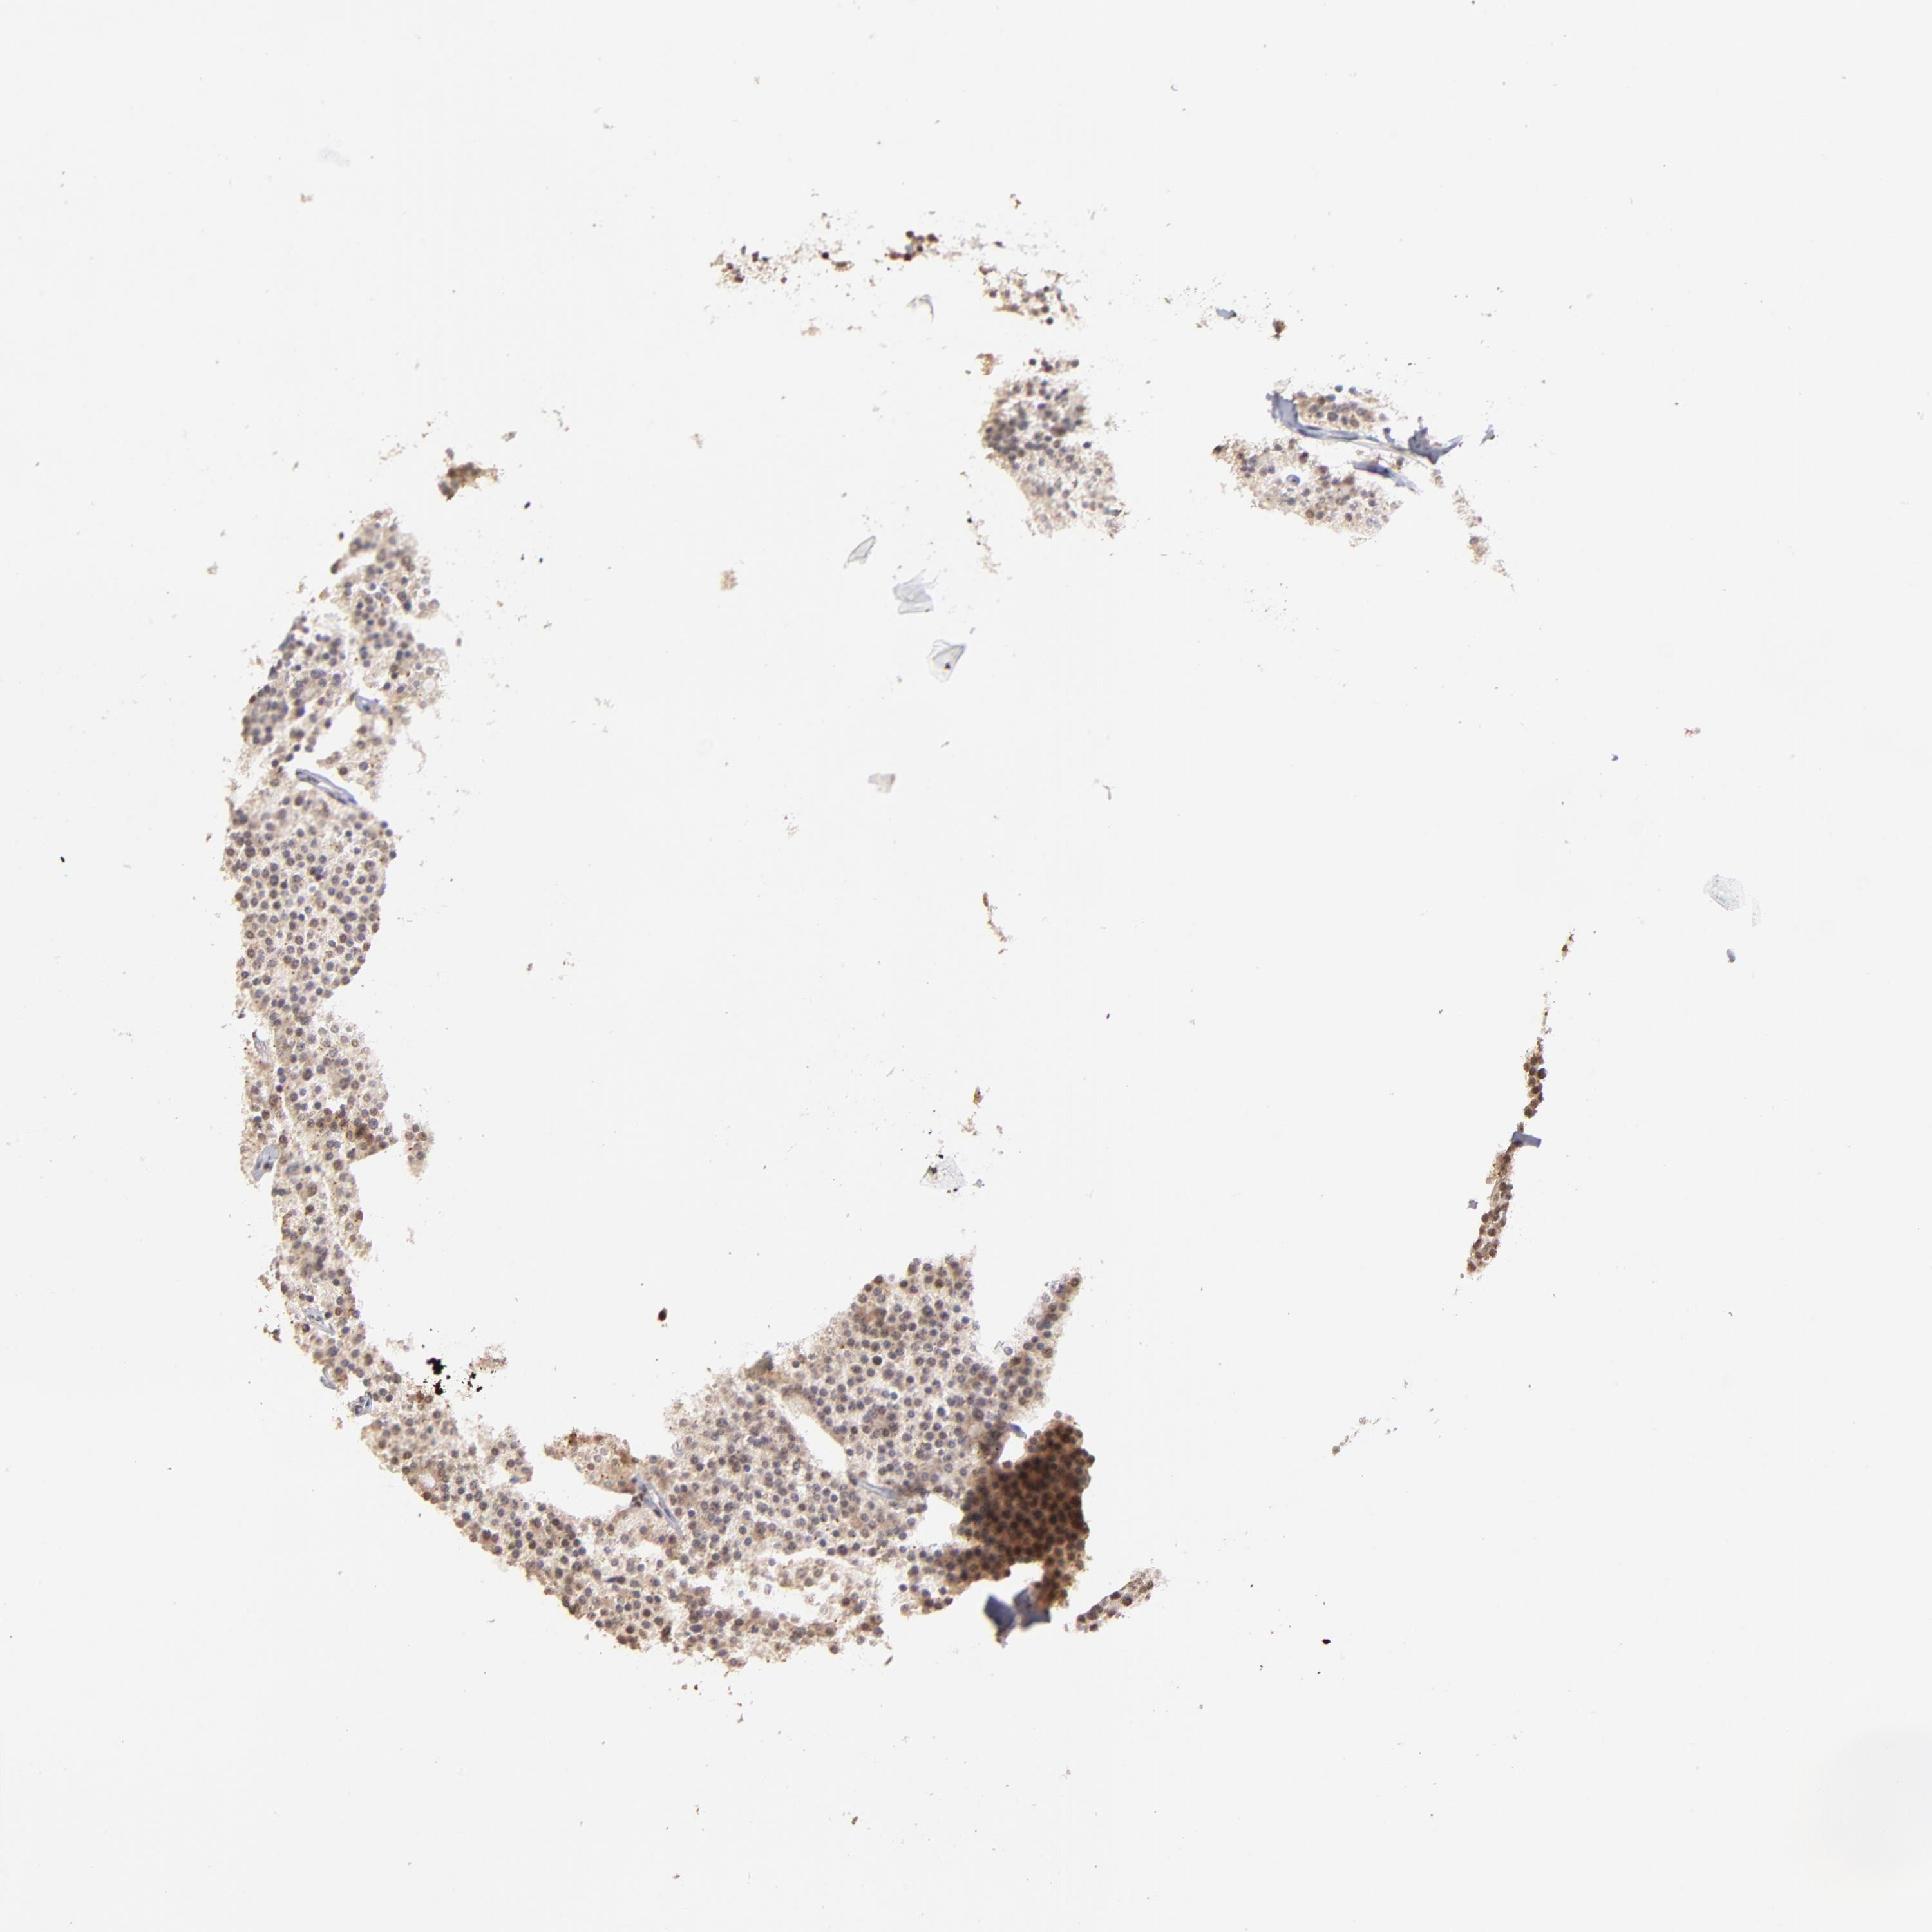

CARCINOID - Protein expressioni

A mouse-over function shows sample information and annotation data. Click on an image to view it in a full screen mode. Samples can be filtered based on level of antibody staining by selecting one or several of the following categories: high, medium, low and not detected. The assay and annotation is described here.

Each image is clickable and will lead to virtual microscopy that enables deeper exploration of all samples and also displays staining intensity scores, fraction scores and subcellular localization as well as patient and tissue information for each sample.

Antibody HPA003142

Staining

High

Strong

>75%

Location

Nuclear

Carcinoid, malignant, NOS